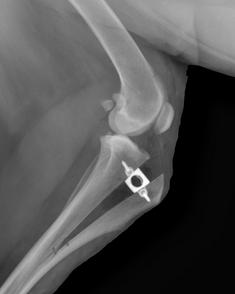

Patella Groove Replacement

Patella Groove replacement TRA Innoplant Implants from 1200€ on